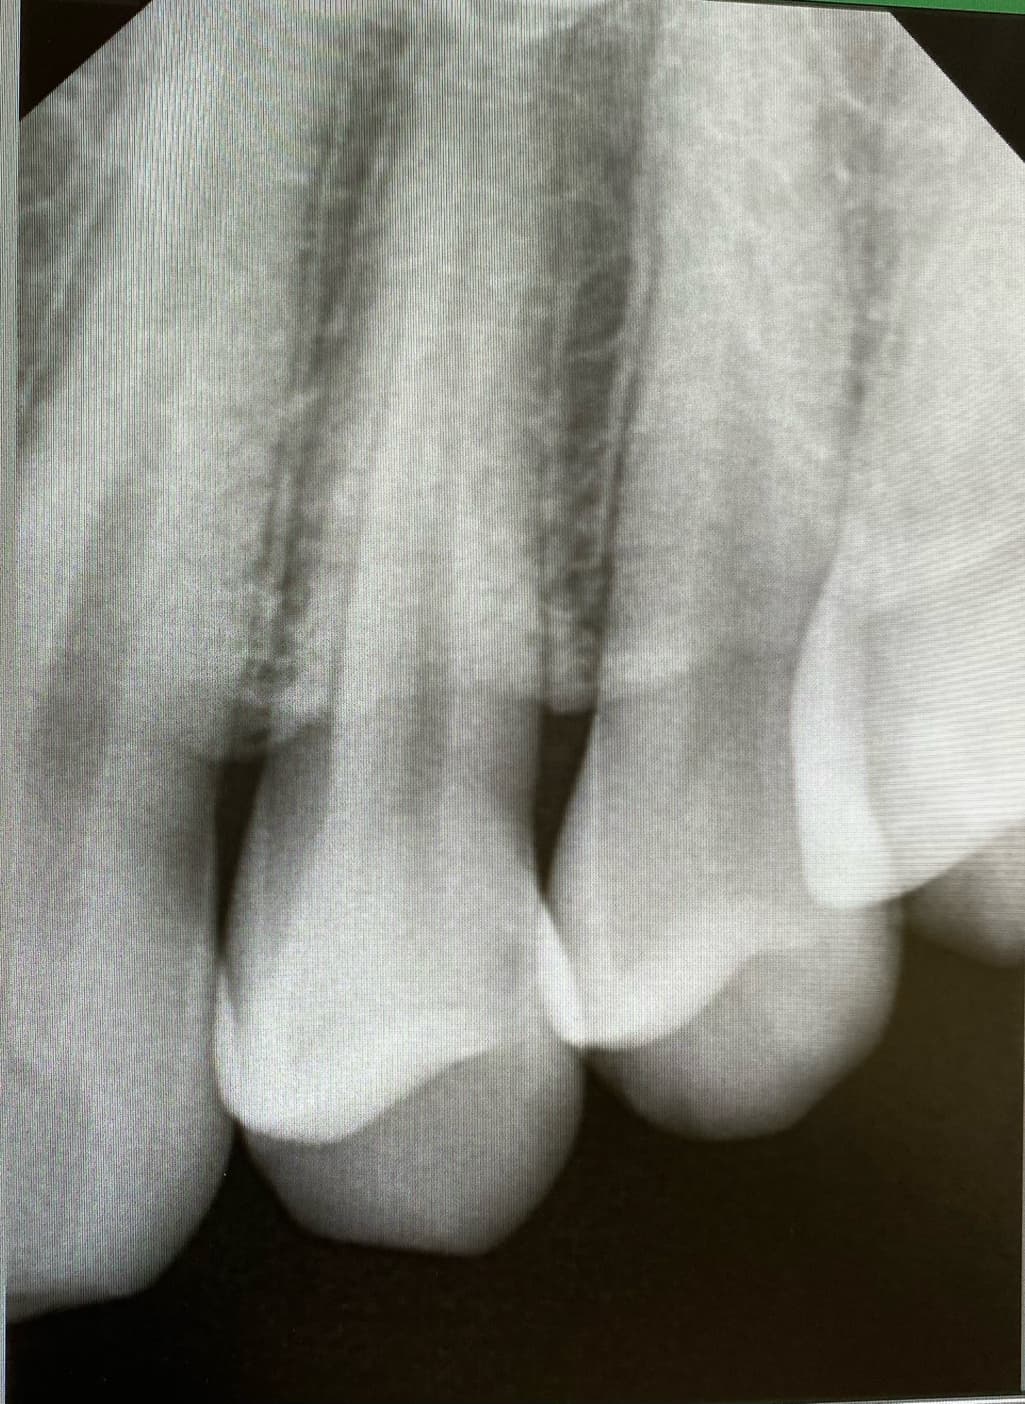

위치 왼쪽 위 2번째 어금니 치료 한 부위 2차 충치

왼쪽 위 4번째와 3번째 사이 인접면 충치

사진에 보이는 정도면 충치가 안쪽에 많이 진행됫을 가능성이 있습니다. 저라면 인레이로 치료를 할것같습니다.

육안으로 보였을 경우 인절면에 충치가 있는 것으로 보입니다. 하지만 방사선상에는 크게 보이진 않습니다. 눈으로 보이는 충치가 있기 때문에 인접면 충치는 치료를 하는 것이 좋을 것으로 생각됩니다.